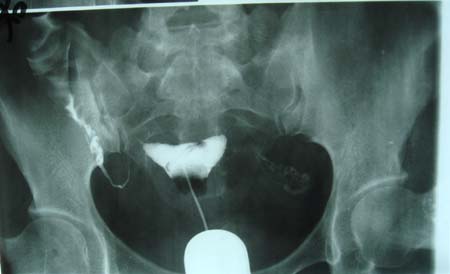

以下是引用dyqct在2009-8-23 16:17:00的发言:[br]考虑:1、造影剂进入腹腔、结肠旁沟、肝周;[br] 2、子宫明显增大(腺肌增生症?);[br] 3、膀胱显影是由于造影剂吸收后经肾分泌进入膀胱的;[br] 4、建议mri检查子宫。